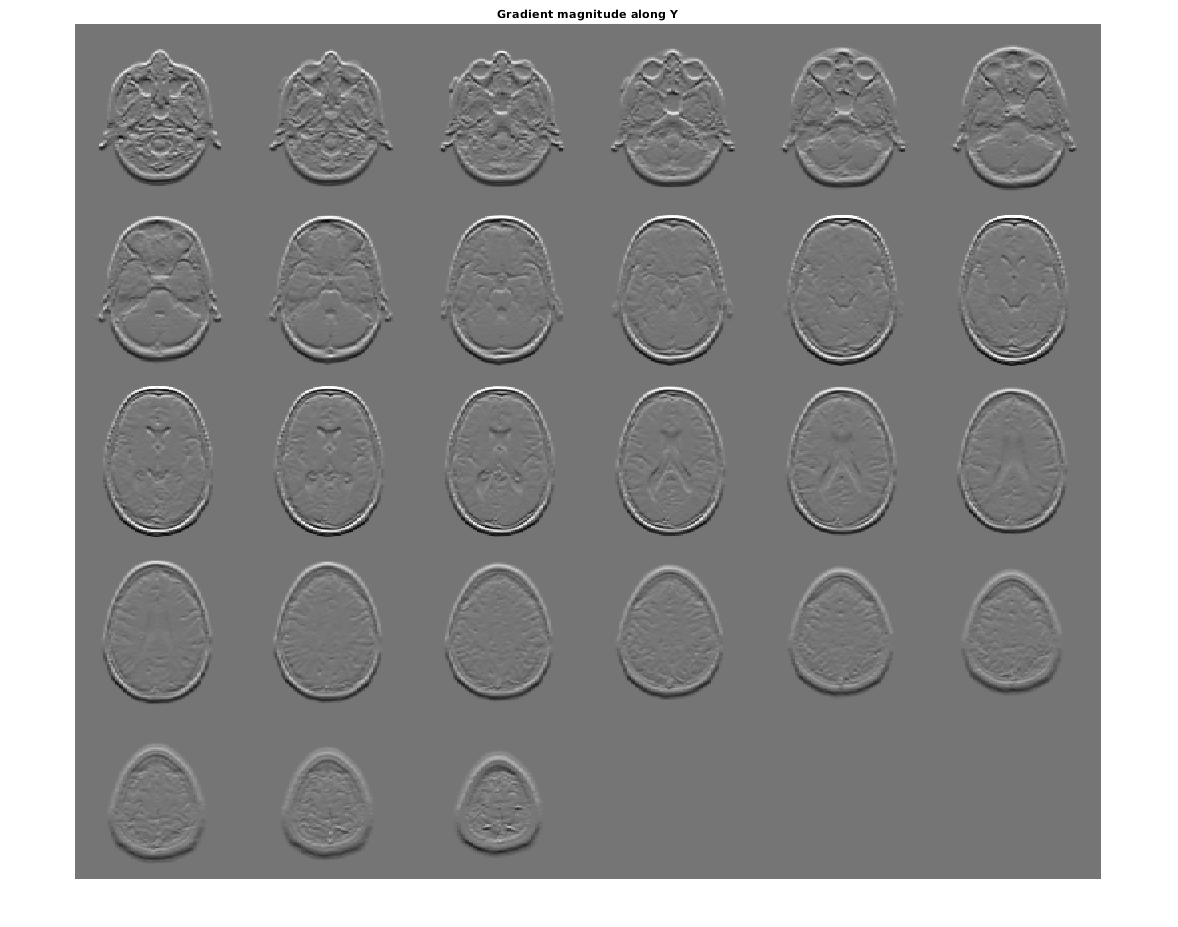

figure, montage(reshape(Gy,sz(1),sz(2),1,sz(3)),'DisplayRange',[])

title('Gradient magnitude along Y')

Figure contains an axes object. The axes object with title Gradient magnitude along Y contains an object of type image.